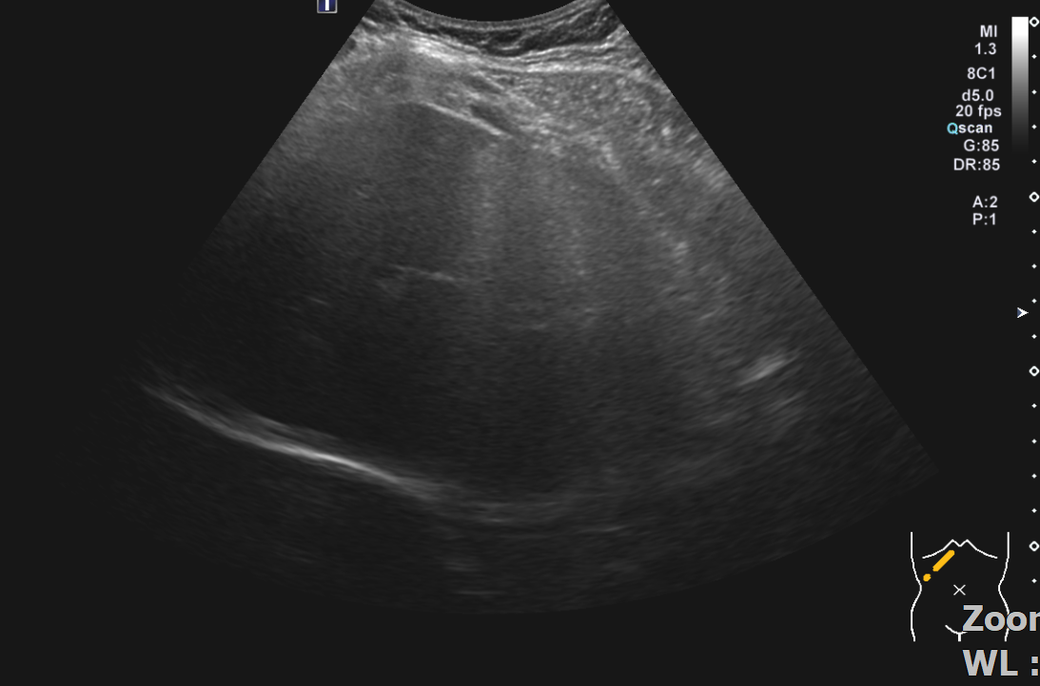

복부초음파 신장 물혹 보이나요? 사진올려봐요

신장물혹 0.6cm mri에는 나오는데 복부초음파에는 소견이없어서요

• 3번 째 사진

올려주신 사진 중 우측 신장이 찍힌 영상은 한 장이며 단면 영상만으로는 물혹 유무를 확인할 수 없습니다.